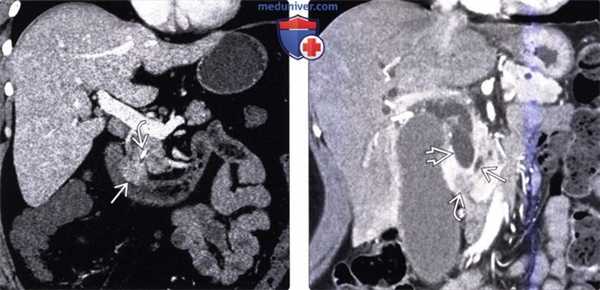

(Слева) На корональной КТ с контрастным усилением визуализируется полиповидное объемное образование (рак) в ампуле фатерова сосочка. Видна также часть билиарного стента ЕЕ. Изображения в корональной плоскости лучше всего позволяют визуализировать ампулу и оценить вероятное объемное образование.

(Справа) На корональной КТ с контрастным усилением визуализируется гиподенсное образование в ампуле, с нечеткими краями, вызывающие обструкцию общего желчного протока, при этом панкреатический проток расширен в незначительной степени. При оперативном вмешательстве был обнаружен рак ампулы фатерова сосочка.